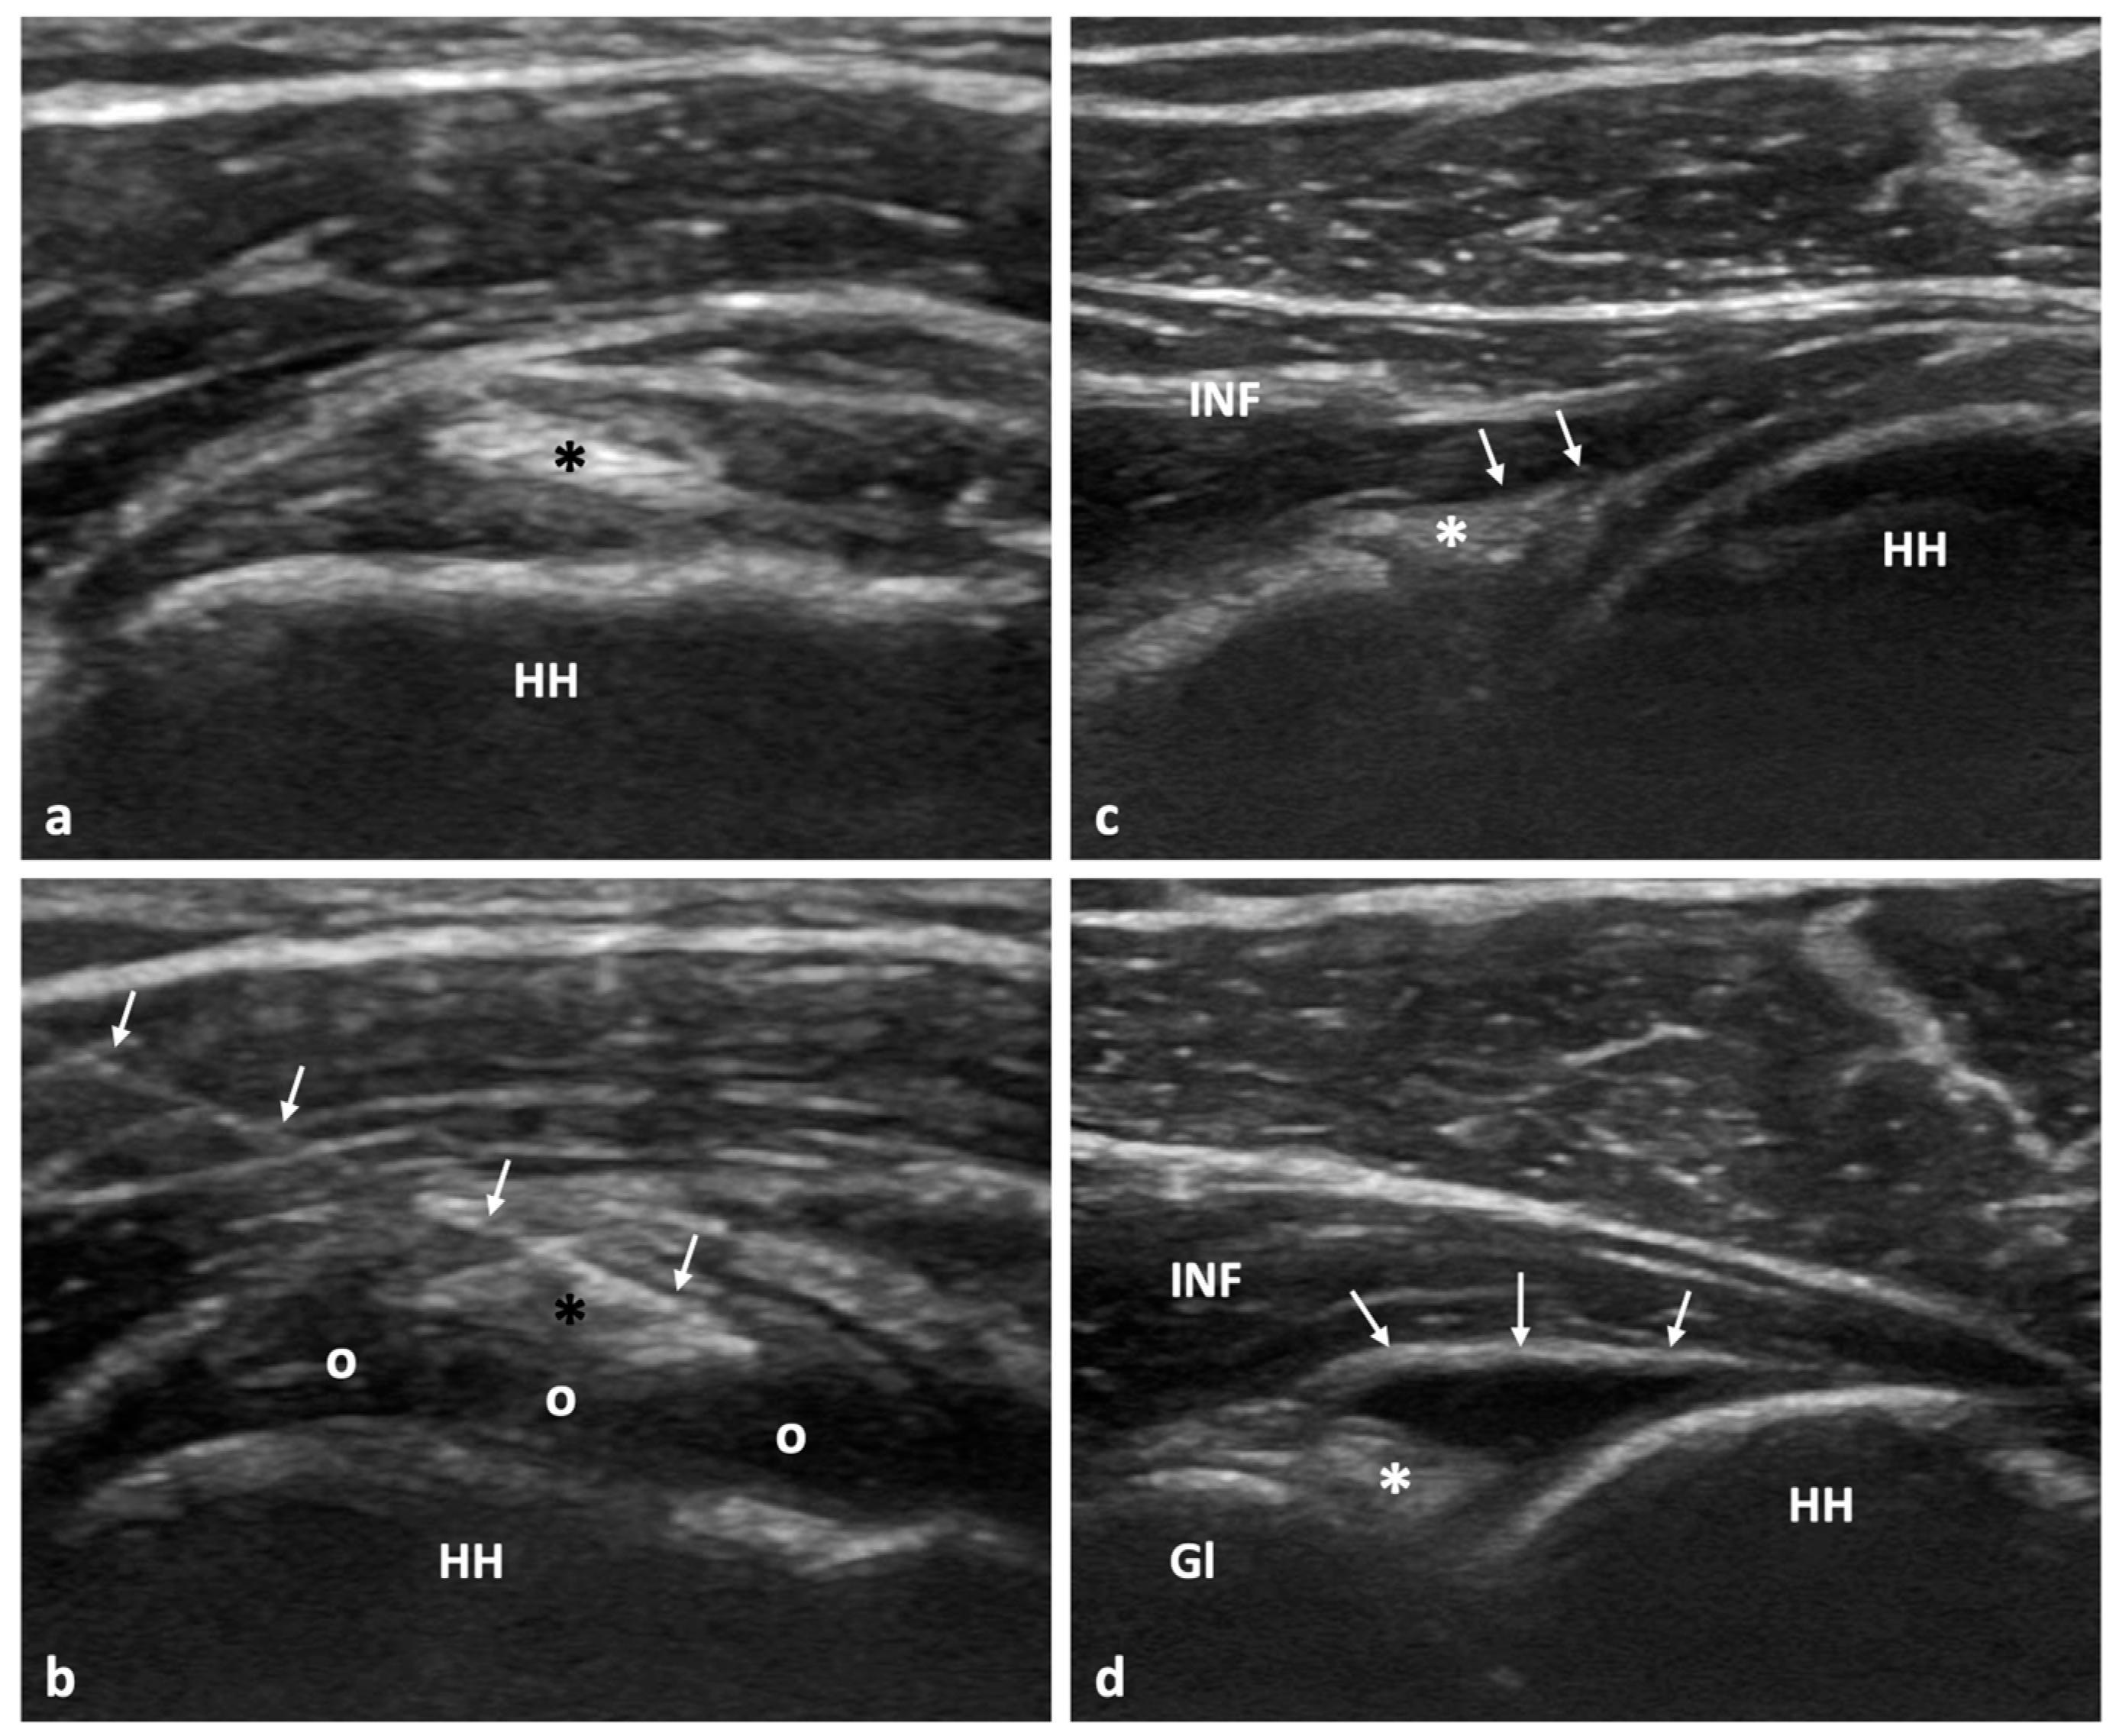

Figure 1 from of Ultrasoundguided Glen Humeral Corticosteroid Injections in Adhesive Adhesive Capsulitis Injection Ultrasound adhesive capsulitis (ac), which is characterised by shoulder pain and a limited range of motion (rom), is usually. adhesive capsulitis, also known as “frozen shoulder,” is a common condition of the shoulder defined as a pathologic process in which contracture of the glenohumeral capsule is a hallmark. adhesive capsulitis (ac) of the shoulder, also referred to as. Adhesive Capsulitis Injection Ultrasound.

Capsular Distension for Adhesive Capsulitis Sports Medicine Review Adhesive Capsulitis Injection Ultrasound adhesive capsulitis, also known as “frozen shoulder,” is a common condition of the shoulder defined as a pathologic process in which contracture of the glenohumeral capsule is a hallmark. adhesive capsulitis (ac), also referred to as ‘frozen shoulder’ and ‘pericapsulitis’, is characterised by progressively worsening. adhesive capsulitis (ac) of the shoulder, also referred to as frozen shoulder,. Adhesive Capsulitis Injection Ultrasound.

Ultrasound Findings of Adhesive Capsulitis Sports Medicine Review Adhesive Capsulitis Injection Ultrasound adhesive capsulitis, also known as “frozen shoulder,” is a common condition of the shoulder defined as a pathologic process in which contracture of the glenohumeral capsule is a hallmark. adhesive capsulitis (ac), also referred to as ‘frozen shoulder’ and ‘pericapsulitis’, is characterised by progressively worsening. adhesive capsulitis (ac) of the shoulder, also referred to as frozen shoulder,. Adhesive Capsulitis Injection Ultrasound.

Figure 5 from Ultrasoundguided hydrodilatation for adhesive capsulitis a stepbystep guide Adhesive Capsulitis Injection Ultrasound adhesive capsulitis, also known as “frozen shoulder,” is a common condition of the shoulder defined as a pathologic process in which contracture of the glenohumeral capsule is a hallmark. adhesive capsulitis (ac), which is characterised by shoulder pain and a limited range of motion (rom), is usually. adhesive capsulitis (ac) of the shoulder, also referred to as. Adhesive Capsulitis Injection Ultrasound.